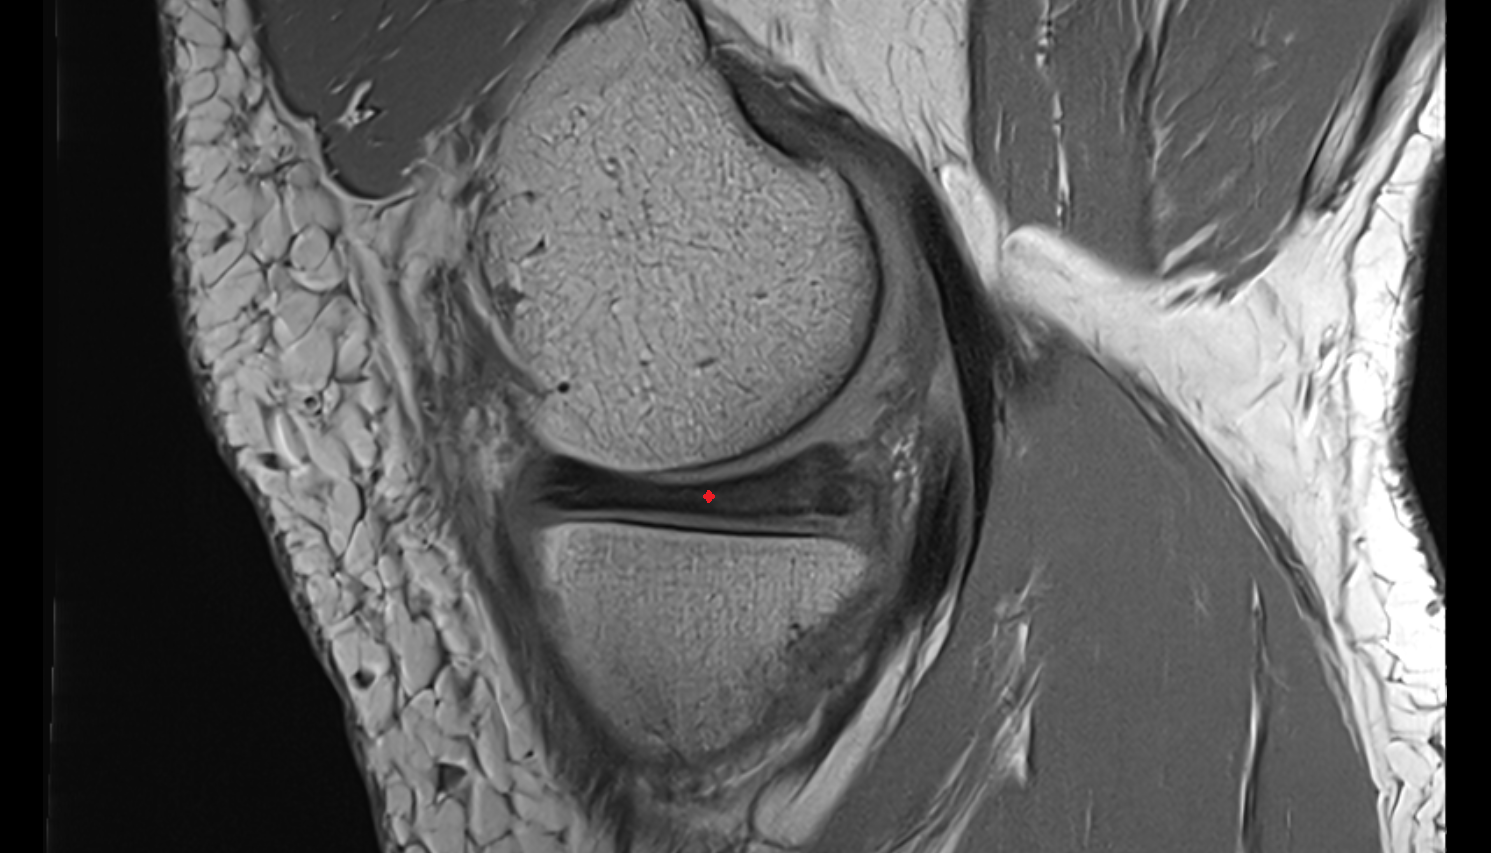

- Anterior cruciate ligament

- Posterior cruciate ligament

- Medial meniscus

- Posterior horn of medial meniscus

- Posterior horn of lateral meniscus